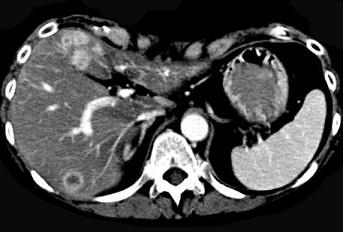

继发性肝癌诊断的关键是 ( )A、行CT检查B、测定血清甲胎蛋白C、行肝动脉造影检查D、行放射核素扫描E、查清原发癌灶

问题 继发性肝癌诊断的关键是 ( )

选项 A、行CT检查 B、测定血清甲胎蛋白 C、行肝动脉造影检查 D、行放射核素扫描 E、查清原发癌灶

答案 E